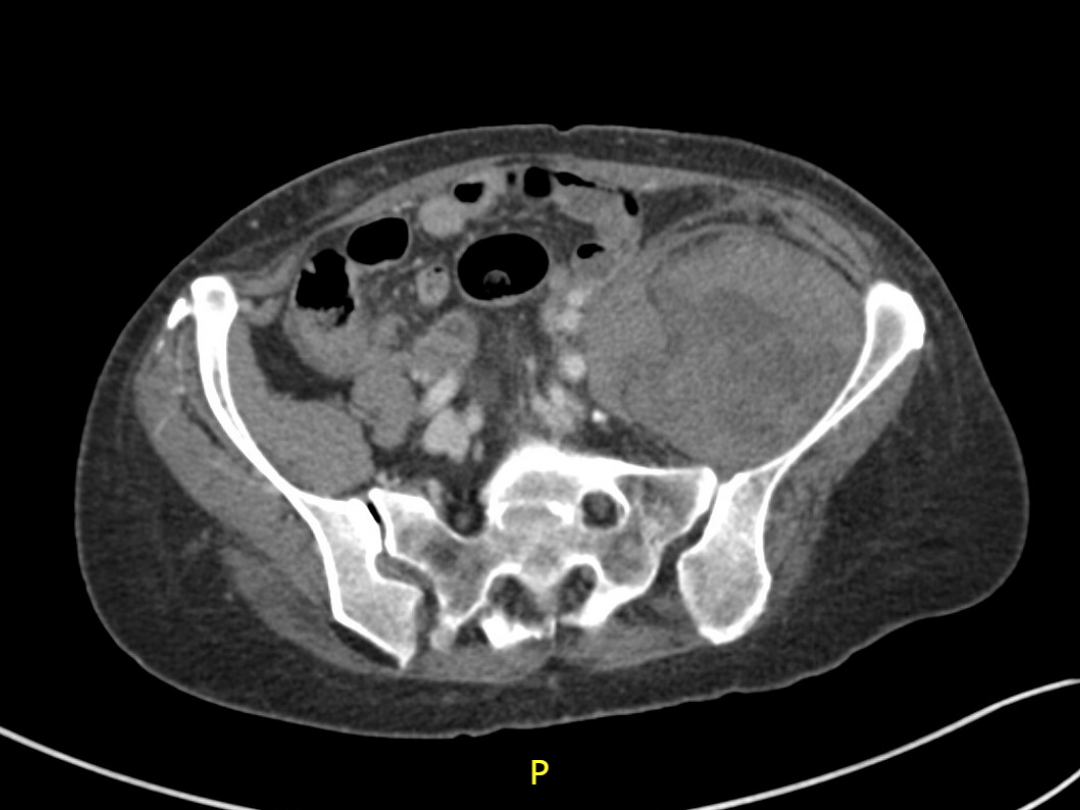

CT-angiogram van het abdomen.

Een 70-jarige vrouw, die werd behandeld met een vitamine K-antagonist, presenteerde zich met spontane pijn aan de linker heup en bovenbeen. Bij klinisch onderzoek merkten we vooral pijn bij actieve heupflexie en passieve heupextensie. Bij CT-angiografie zagen we een M.-iliacushematoom, met een actieve arteriële bloeding. De patiënte onderging een urgente embolisatie van de aanvoerende pelviene-arterietakken.